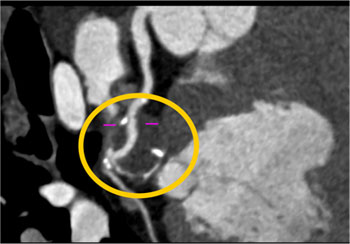

Aneurysm of Circumflex Coronary Artery 27 year old female with symptoms of increasing fatigue and pulsation in the left chest and neck. CTA demonstrates a persistent left SVC and aneurysm of the circumflex coronary artery.

Dx-Aneurysm of the Circumflex Coronary Artery In this patient the cause of the coronary artery aneurysm was atherosclerotic disease and could best be managed by surgical intervention. The patient ultimately decided against any intervention.